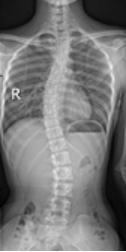

保护“未来脊梁”——关注青少年脊柱侧弯

保护“未来脊梁”——关注青少年脊柱侧弯保护“未来脊梁”---关注青少年脊柱侧弯你家孩子是否写作业时老是扭动身体?经常感觉腰背酸痛?双肩不一样高?频繁出现领口不平?裙摆不在同一水平线上?究竟是什么原因引起的?大家要警惕,有可能是青少年脊柱侧弯惹…查看详情+